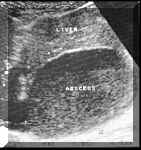

The

margins

of

abscess

may

be

ill

defined,

is

hypoechoic

as

compared

to

surrounding

liver.

However,

there

no

true

liquefaction

at

this

stage

and

therefore

poor

or

posterior

acoustic

enhancement.

demarcation

between

liver

also

(see

Picture1).

Picture1.

Early

[1].